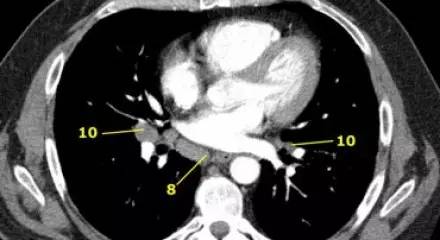

隆突下肺 CT 横断面上的隆突以下食管旁淋巴结(8)、肺门淋巴结(10)